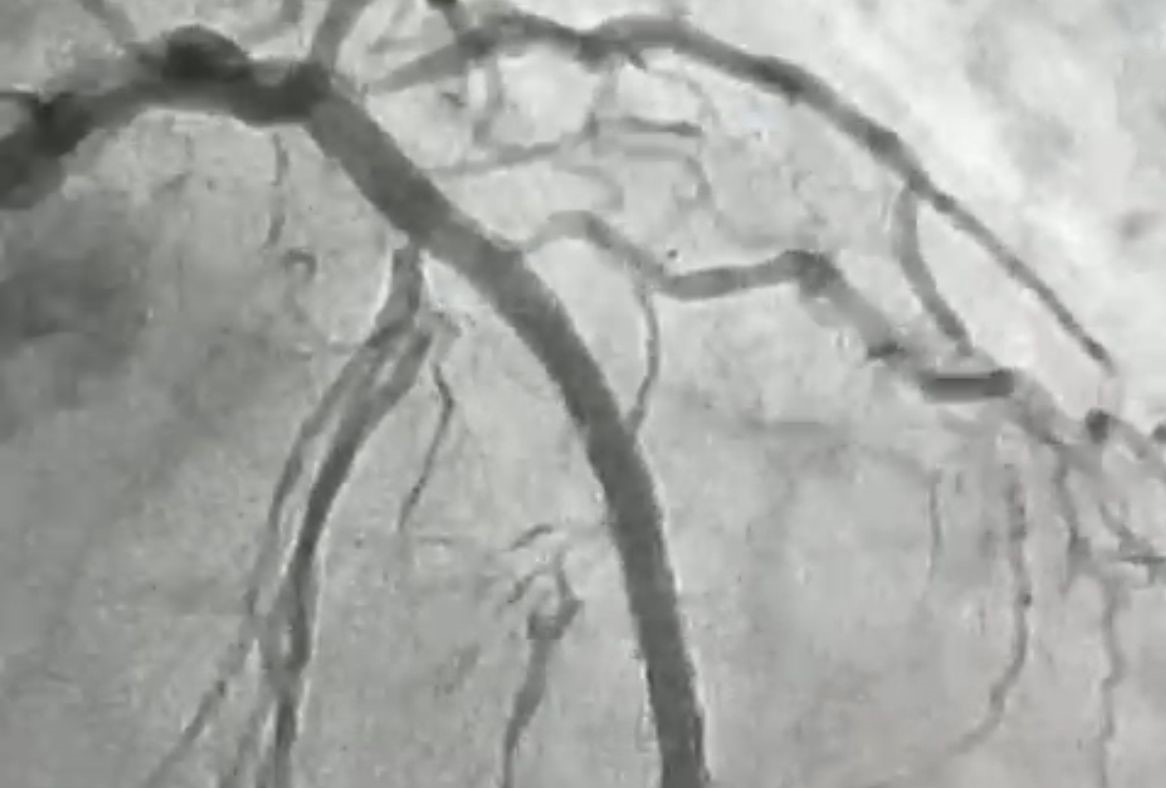

O procedimento foi realizado em uma paciente de 84 anos, moradora de Itaporanga, que apresentava uma lesão grave e altamente calcificada na artéria descendente anterior, considerada a principal artéria do coração. Segundo o cardiologista intervencionista, Jeann Santiago, um dos médicos responsáveis pela realização do procedimento, a condição exigia um tratamento extremamente delicado, com risco elevado, devido à dureza da placa obstrutiva, comparada pelos médicos a uma “pedra” no interior do vaso.

“Para possibilitar a abertura da artéria, a equipe utilizou a aterectomia rotacional, técnica que funciona como uma microfuradeira capaz de desgastar e desobstruir placas de cálcio muito rígidas. Em seguida, com o auxílio do ultrassom intravascular, foi possível medir com precisão a extensão da lesão e determinar o tamanho ideal dos dispositivos a serem implantados. Após a preparação do vaso, foram colocados dois stents farmacológicos, completando o processo de revascularização”, explicou o cardiologista.